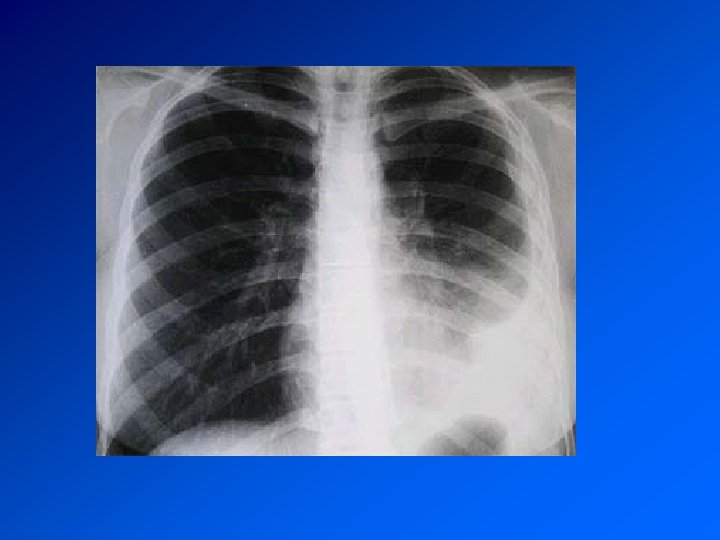

Pneumothorax • présence d’air dans la cavité pleurale • Le plus souvent rupture de la plèvre viscérale avec issue d’air des alvéoles sous pleurales dans la cavité pleurale • Plus rarement arrivée d’air de l’extérieur : plaie pénétrante du thorax et PNT iatrogène

PNT spontanée du sujet jeune Le pneumothorax est lié à la rupture de bulles d’air sous -pleurales. CDD : douleur thoracique brutale spontanée ou lors d’un effort. Parfois dyspnée Examen : tympanisme hémithoracique. Recherche de signes de détresse respiratoire (polypnée, cyanose, sueur, tirage…) Radio : hyperclarté périphérique séparée du poumon par le « liséré capillaire » : image de la plèvre viscérale. La radio fait le diagnostic